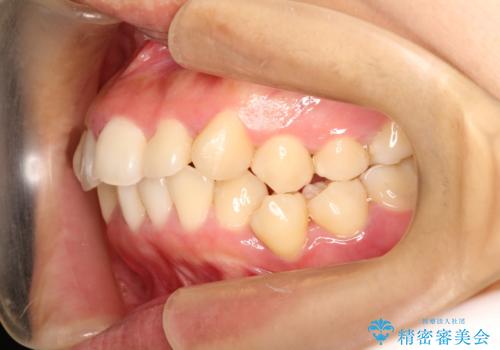

上下の歯のガタガタ ワイヤーでの抜歯矯正で整った歯並びへ

- 上下の歯のガタガタを治したいとのことで来院されました。

がたつきの度合いが強いのと、口元をなるべく引っ込めたい希望がありましたので、ワイヤーでの抜歯矯正となりました。

ガタガタが重度の方は抜歯が必要となることが多いです。

抜歯スペースを使って前歯を引っ込めることにより、口元の突出感も改善できました。